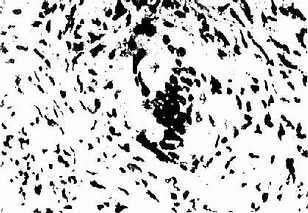

结节病肉芽肿在组织切片上可见为皮样细胞的聚集,其中有多核巨噬细胞,周围有淋巴细胞,而无干酪样病变(图2-11-1)。在巨噬细胞的泡浆中可见有包涵体,如卵圆形的舒曼(Schaumann)小体,双折光的结晶和星状小体(asteroid body)(图2-11-2)。肺结节病的初发病变有较广泛的单核细胞、巨噬细胞、淋巴细胞浸润的肺泡炎,累及肺泡壁和间质。肺泡炎和肉芽肿都可能自行消散。但在慢性阶段,肉芽肿周围的纤维母细胞胶原化和玻璃样,成为非特异性的纤维化。肉芽肿的组织形态学表现并无特性,可见于分支杆菌和真菌感染,或为异物或外伤的组织反应,亦可见于铍病、第三期梅毒淋巴瘤和外源性变态反应性肺泡炎等,应行鉴别。但在多器官中见到同样的组织病变,结合临床资料,可诊断本病。

结节病肉芽肿

图2-11-1 结节病肉芽肿

结节主要由类上皮细胞组成,中央无干酪样坏死,周围淋巴细胞少,边界清楚